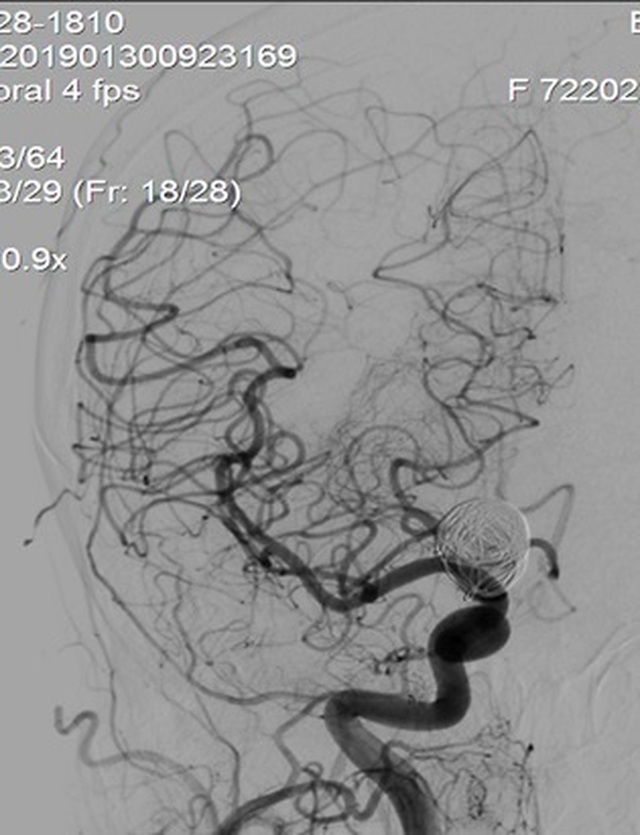

Kết quả chụp DSA phát hiện túi phình khổng lồ ở động mạch cảnh trong bên phải trong não bệnh nhân H. Đoạn động mạch mắt có kích thước 17 x 30mm và được xem là lớn nhất từ trước tới nay tại Bệnh viện Trung ương Huế và nếu túi phình vỡ thì tỉ lệ tử vong gần như tuyệt đối.

Túi phình khổng lồ động mạch cảnh trong phải

Đặt các vòng xoắn kim loại vào túi phình để tắc một phần túi phình